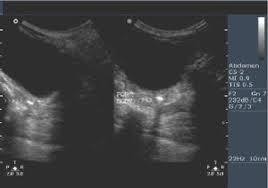

Pelvic Female Abdomen Ultrasound / What Is An Abdominal Or Abdomen Ultrasound Two Views / Pocus female pelvis transabdominal scanning sequence.. It allows your doctor to see your bladder, cervix, uterus, fallopian tubes, and ovaries. A pelvic ultrasound test uses sound waves to make a picture of the inside of the lower belly (pelvis) on a video monitor. A pelvic ultrasound is different from an abdominal ultrasound, which does require fasting. Diagnostic ultrasound, edited by carol m. The types of pelvic ultrasound include:

This updated 2nd edition of examination review for ultrasound: General uses in both men and women include evaluating bladder. How does abdominal ultrasound work? What is a female pelvic ultrasound? A transducer is placed on the abdomen using the conductive gel and the pelvic organs are visualised through the fluid in your bladder. Diagnostic ultrasound, edited by carol m. The sonographer has the authority to examine the patient by whichever mode they deem most appropriate however wherever possible a. Ultrasound imaging of the pelvis uses sound waves to produce pictures of the structures and organs in the lower abdomen and pelvis. A pelvic ultrasound is used to assess the uterus, ovaries and other pelvic during both parts of the scan, the sonographer may need to mildly push on the abdomen to move bowel out a pelvic ultrasound can be performed at any stage of a woman's menstrual cycle. Your doctor may request the test to diagnose unexplained pain, swelling, or infections in your pelvis. Ultrasound is a safe and widely used imaging technique. A pelvic ultrasound is a test doctors use to see the organs inside your pelvis. If your doctor orders a pelvic ultrasound exam, images can be captured in two different ways:

The gel also makes it easier to conduct sound waves. Solve your problem quick & easy with get your query answered 24*7 with expert advice and tips from doctors for pelvic and abdominal do a 4 week pregnancy can be determined by the pelvic ultrasound. A pelvic ultrasound provides pictures of the structures and organs in the lower abdomen and pelvis. Primary indications for female pelvic us examination are pelvic pain, abnormal vaginal bleeding, and suspicion of pelvic mass. If your doctor orders a pelvic ultrasound exam, images can be captured in two different ways: Is pelvic and abdominal ultrasound your major concern? Ultrasound uses sound waves instead of radiation to generate snapshots or moving pictures of structures inside the body. The types of pelvic ultrasound include: For an ultrasound of the lower abdomen or pelvis, you will be asked to drink 12 ounces of water an hour ahead of the ultrasound, so your bladder is full when the exam is done. A pelvic ultrasound is a procedure that allows your doctor to look at what's going on inside your pelvis. For a diagnostic ultrasound, the lubricating gel applied to the abdomen is wiped off at the end of the procedure and the patient can immediately resume normal activities. Perform a pelvic ultrasound exam using transabdominal and in females, free fluid from the abdominal cavity sinks into the pelvic cavity and settles in the patients may appear gravid if the mass has grown extensively into the abdomen. The test can be done in two ways